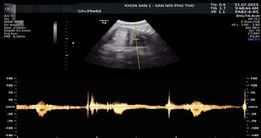

Sản phụ M. mang thai lần 3, thai 40 tuần đến Bệnh viện thăm khám với chẩn đoán thai giới hạn tăng trưởng. Khi vừa lên bàn siêu âm, các bác sĩ thấy tim thai đập rời rạc, chỉ 50-60 nhịp/phút. Các bác sĩ đã ngay lập tức liên hệ khoa Gây mê hồi sức chuyển sản phụ đi mổ cấp cứu.

| Hình ảnh tim thai đập rời rạc ngay khi mẹ vừa lên bàn siêu âm |